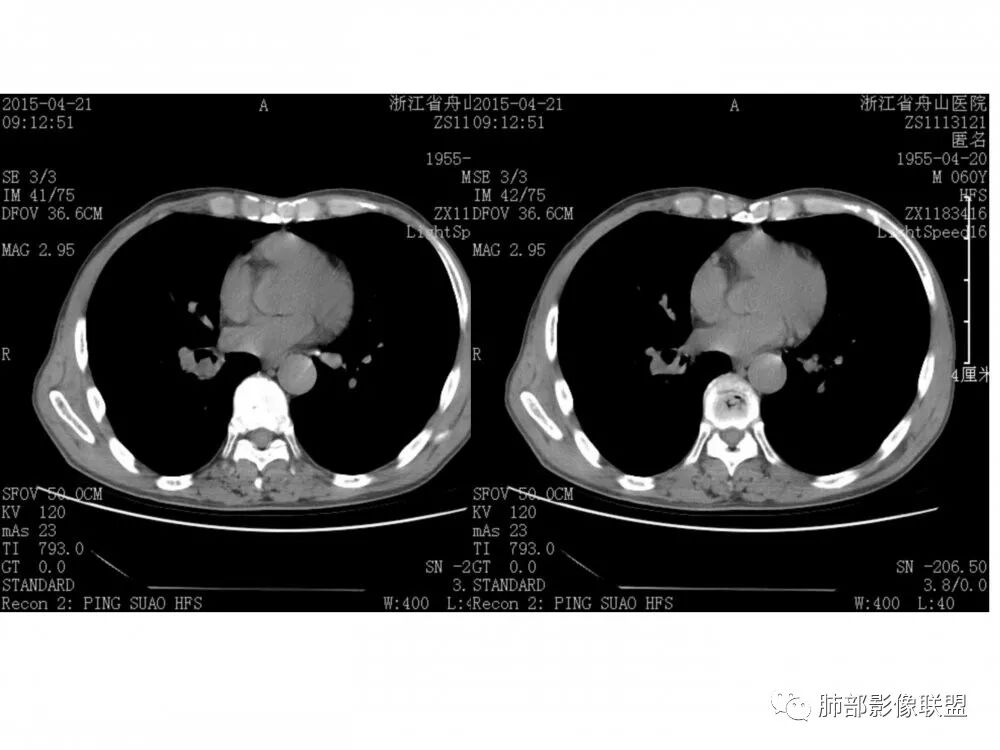

老年男性,右下基底外压狭窄,11、10、7、4、2组淋巴结肿大,考虑小细胞

右肺下叶基底段支气管旁结节,低强化,支气管受压变窄,软骨连续未见破坏,右肺门及纵隔多发淋巴结增大,低强化与结节强化一致,考虑小细胞肺癌可能

老年男性,右肺下叶支气管腔内肿块,轻度强化,纵隔淋巴结多发肿大,无阻塞性炎症,常规考虑恶性,小细胞可能,类癌代排。

老年男性,右肺下叶支气管腔狭窄,见低强化软组织密度结节突向腔内,局部支气管壁破坏消失,邻近血管受压推移,纵膈内及右肺门区淋巴结肿大。综合考虑小细胞肺癌(SCLC)可能性大,鉴别类癌及鳞癌。

老年男性,右肺下叶支气管腔内可见软组织密度影,向腔内突入,支气管壁破坏,向外突出,管腔明显狭窄,增强后轻度强化,伴纵膈及肺门多发肿大淋巴结,首先考虑恶性肿瘤,小细胞肺癌可能大,建议支气管镜检查